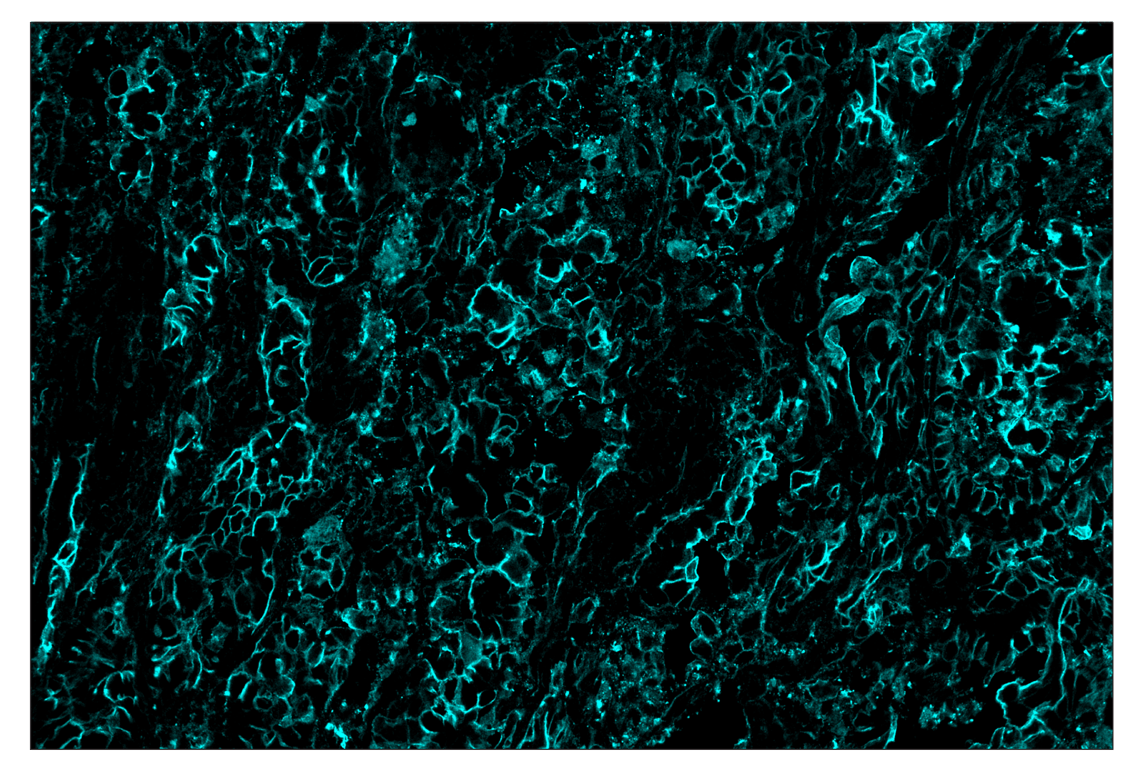

SignalStar multiplex immunohistochemistry (mIHC) is a tool that employs antibodies, oligonucleotides (oligos), and fluorophores to interrogate the cellular presence, location, function, and biomarker co-expression patterns. SignalStar technology enables the detection of multiple phenotypic and functional targets while maintaining spatial context and tissue architecture. These insights are essential for understanding how cells organize and interact to influence the tissue microenvironment and drive disease progression and response to therapy.

The power of the SignalStar system lies in the design of the SignalStar antibodies. These antibodies have been rigorously validated for use in formalin-fixed, paraffin-embedded (FFPE) tissues, and subsequently conjugated to unique oligo tags using site-specific conjugation and thorough purification methodologies. Using a highly specific network of complementary oligos and fluorophores, scientists can amplify the signal for 3-8 targets, even if they are in low abundance.

Figure 1. All antibodies in your plex size of choice (3-8 maximum unique oligo-conjugated antibodies) are added in cocktail in one primary incubation step. Complementary oligos with fluorescent dyes (channels: 488, 594, 647, and 750) amplify the signal of up to 4 oligo-conjugated antibodies in the first round of imaging by building oligo-fluorophore constructs attached to the antibody. If the plex size is greater than 4, the first round of oligos and fluorophores are gently removed, and a second round of amplification is performed to visualize up to 4 additional oligo-conjugated antibodies; the complementary oligo system and the use of the fluorophore removal process enables a second round of antibodies to be amplified from the same substrate, without cross-reactivity. The 2 images are then aligned and fused computationally with either proprietary or open-source software to generate an image consisting of up to 8 targets.

SignalStar™ Multiplex Immunohistochemistry (mIHC) is a technology that employs antibodies, oligonucleotides (oligos), and fluorophores to interrogate cellular presence, location, function, and biomarker co-expression patterns. SignalStar technology enables the detection of multiple phenotypic and functional targets while maintaining spatial context and tissue architecture. These insights are essential for understanding how cells organize and interact to influence the tissue microenvironment and drive disease progression and response to therapy.

The power of the SignalStar system lies in the design of the SignalStar antibodies. These antibodies have been rigorously validated for use in formalin-fixed, paraffin-embedded (FFPE) tissues, and subsequently conjugated to unique oligo tags using site-specific conjugation and thorough purification methodologies. Using a highly specific network of complementary oligos and fluorophores, scientists can amplify the signal for 3-8 targets, even if they are in low abundance.

Figure 1. All antibodies in your plex size of choice (3-8 maximum unique oligo-conjugated antibodies) are added in cocktail in one primary incubation step. Complementary oligos with fluorescent dyes (channels: 488, 594, 647, and 750) amplify the signal of up to 4 oligo-conjugated antibodies in the first round of imaging by building oligo-fluorophore constructs attached to the antibody. If the plex size is greater than 4, the first round of oligos and fluorophores are gently removed, and a second round of amplification is performed to visualize up to 4 additional oligo-conjugated antibodies; the complementary oligo system and the use of the fluorophore removal process enables a second round of antibodies to be amplified from the same substrate, without cross-reactivity. The 2 images are then aligned and fused computationally with either proprietary or open-source software to generate an image consisting of up to 8 targets.